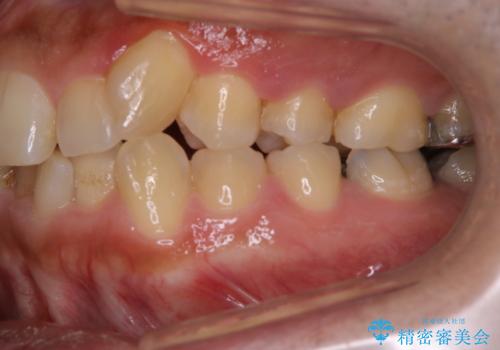

前歯メインにステインの付着が見られ、コース内容を相談した結果PMTC(保険外治療)の30分コースを行いました。